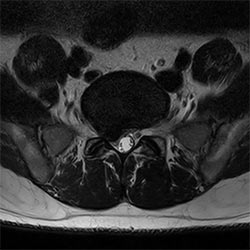

MR görüntülemeyi birçok farklı kontrast tiplerinde ve sekanaslarda yapabilen, 2D ve 3D görüntülemeleri hızlandıran Compressed SENSE hakkında daha detaylı bilgilenmek için Kantonsspital Winterthur'ın (İsviçre) deneyimlerinden faydalanın.